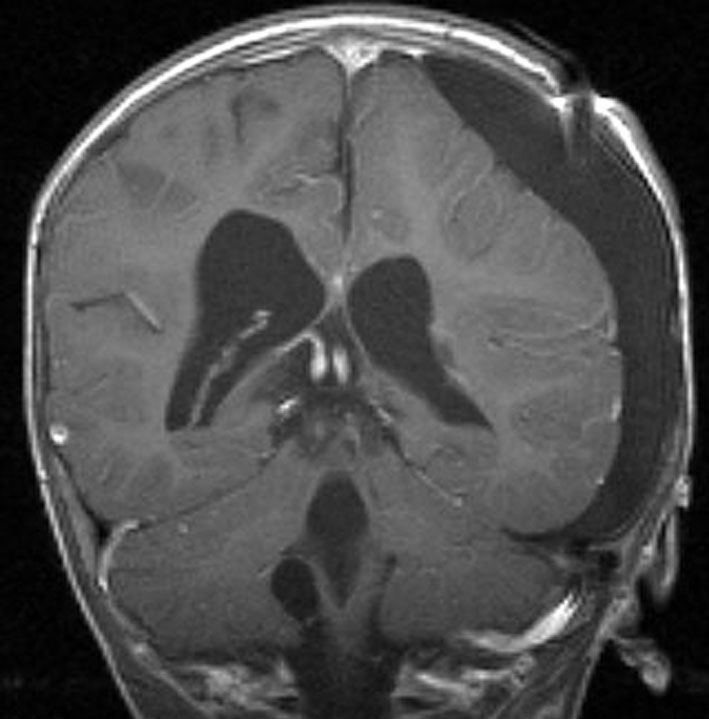

1歳児の巨大な脈絡叢乳頭腫です。このくらいのサイズになると手術で出血死することもあります。右側の画像は手術後のMRIで幸い全摘出できています。乳幼児のこのように巨大なものでは無理して全摘出にいどまないで,シャントをして水頭症を改善して,化学療法で腫瘍を小さくしてから,開頭手術するという方法もあるでしょう。執刀医の経験値で判断は異なります。